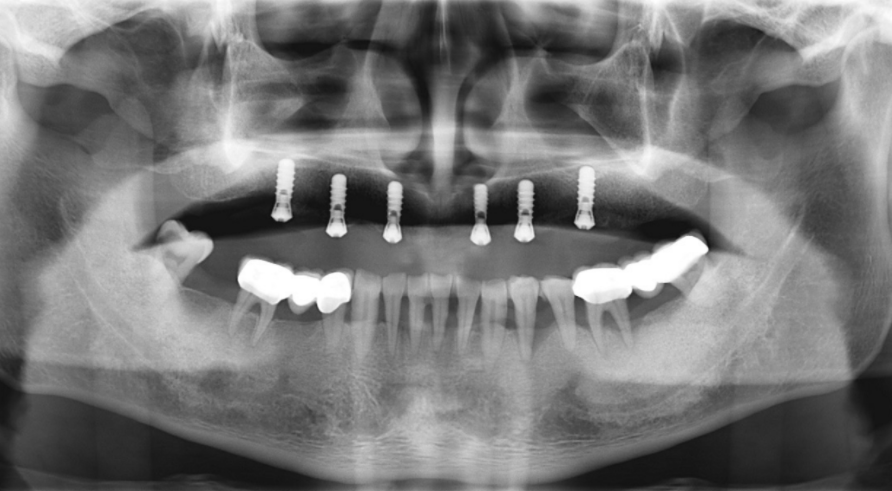

Рентгенопроникні маркери для проведення конусно-променевої томографії були прикріплені до існуючого суцільного верхнього протезу пацієнта, який потім просканували за допомогою апарату ProMax 3D Mid для проведення конусно-променевої комп'ютерної томографії.

Ротова порожнина пацієнта, із встановленим протезом на місце, була просканована тим самим апаратом для комп'ютерної томографії. Скан протезу був співставлений із записом комп'ютерної томографії верхньої щелепи задля планування оптимального протезування на імплантах. (зображення 1 та 2)

Також був зроблений і післяхірургіний панорамний рентгенний знімок. (зображення 7)